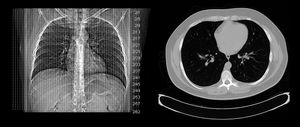

; 폐

CT 스캔은 폐 조직의 급성 및 만성 변화를 모두 감지하는 데 사용된다.[41] 일반적인 2차원 X-레이는 이러한 결함을 나타내지 않기 때문에 이 경우 특히 유용하다.

폐기종 및 섬유증과 같은 만성 간질성 과정 평가를 위해[42] 높은 공간 주파수 재구성을 사용한 얇은 단면을 사용하며, 흡기와 호기 모두에서 스캔을 수행하기도 한다. 이 특수 기술은 고해상도 CT라고 불린다.[43]